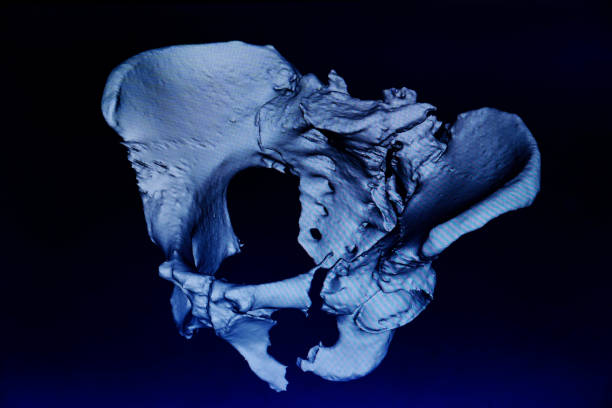

골반 통증 원인 다섯 번째는 대퇴골두 무혈성 괴사입니다. 이름은 어렵지만 대퇴 골두 무혈성 괴사의 경우 넓적다리 위쪽에서 대퇴 골두로 가게 하는 혈액의 흐름을 차단하기 때문에 뼈 조직이 죽으며 엉덩이 부위와 골반 통증을 유발하는 질병입니다. 따라서 괴사가 발생하더라도 초기에는 아무런 증상을 느낄 수 없다는 점이 특징이기 때문에 조금의 통증이라도 느껴지면 빠른 진료가 필요하며 심해지면 고관절의 손상으로 이어지게 되어 주의가 필요합니다.